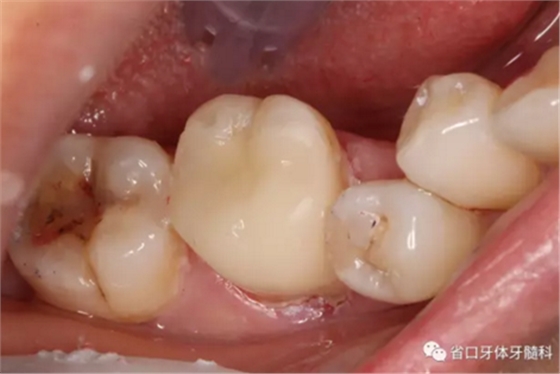

圖3 牙體預備后,近中頰側牙體缺損平齊齦緣;近頰根管口流動樹脂覆蓋牙膠不足,下次改進